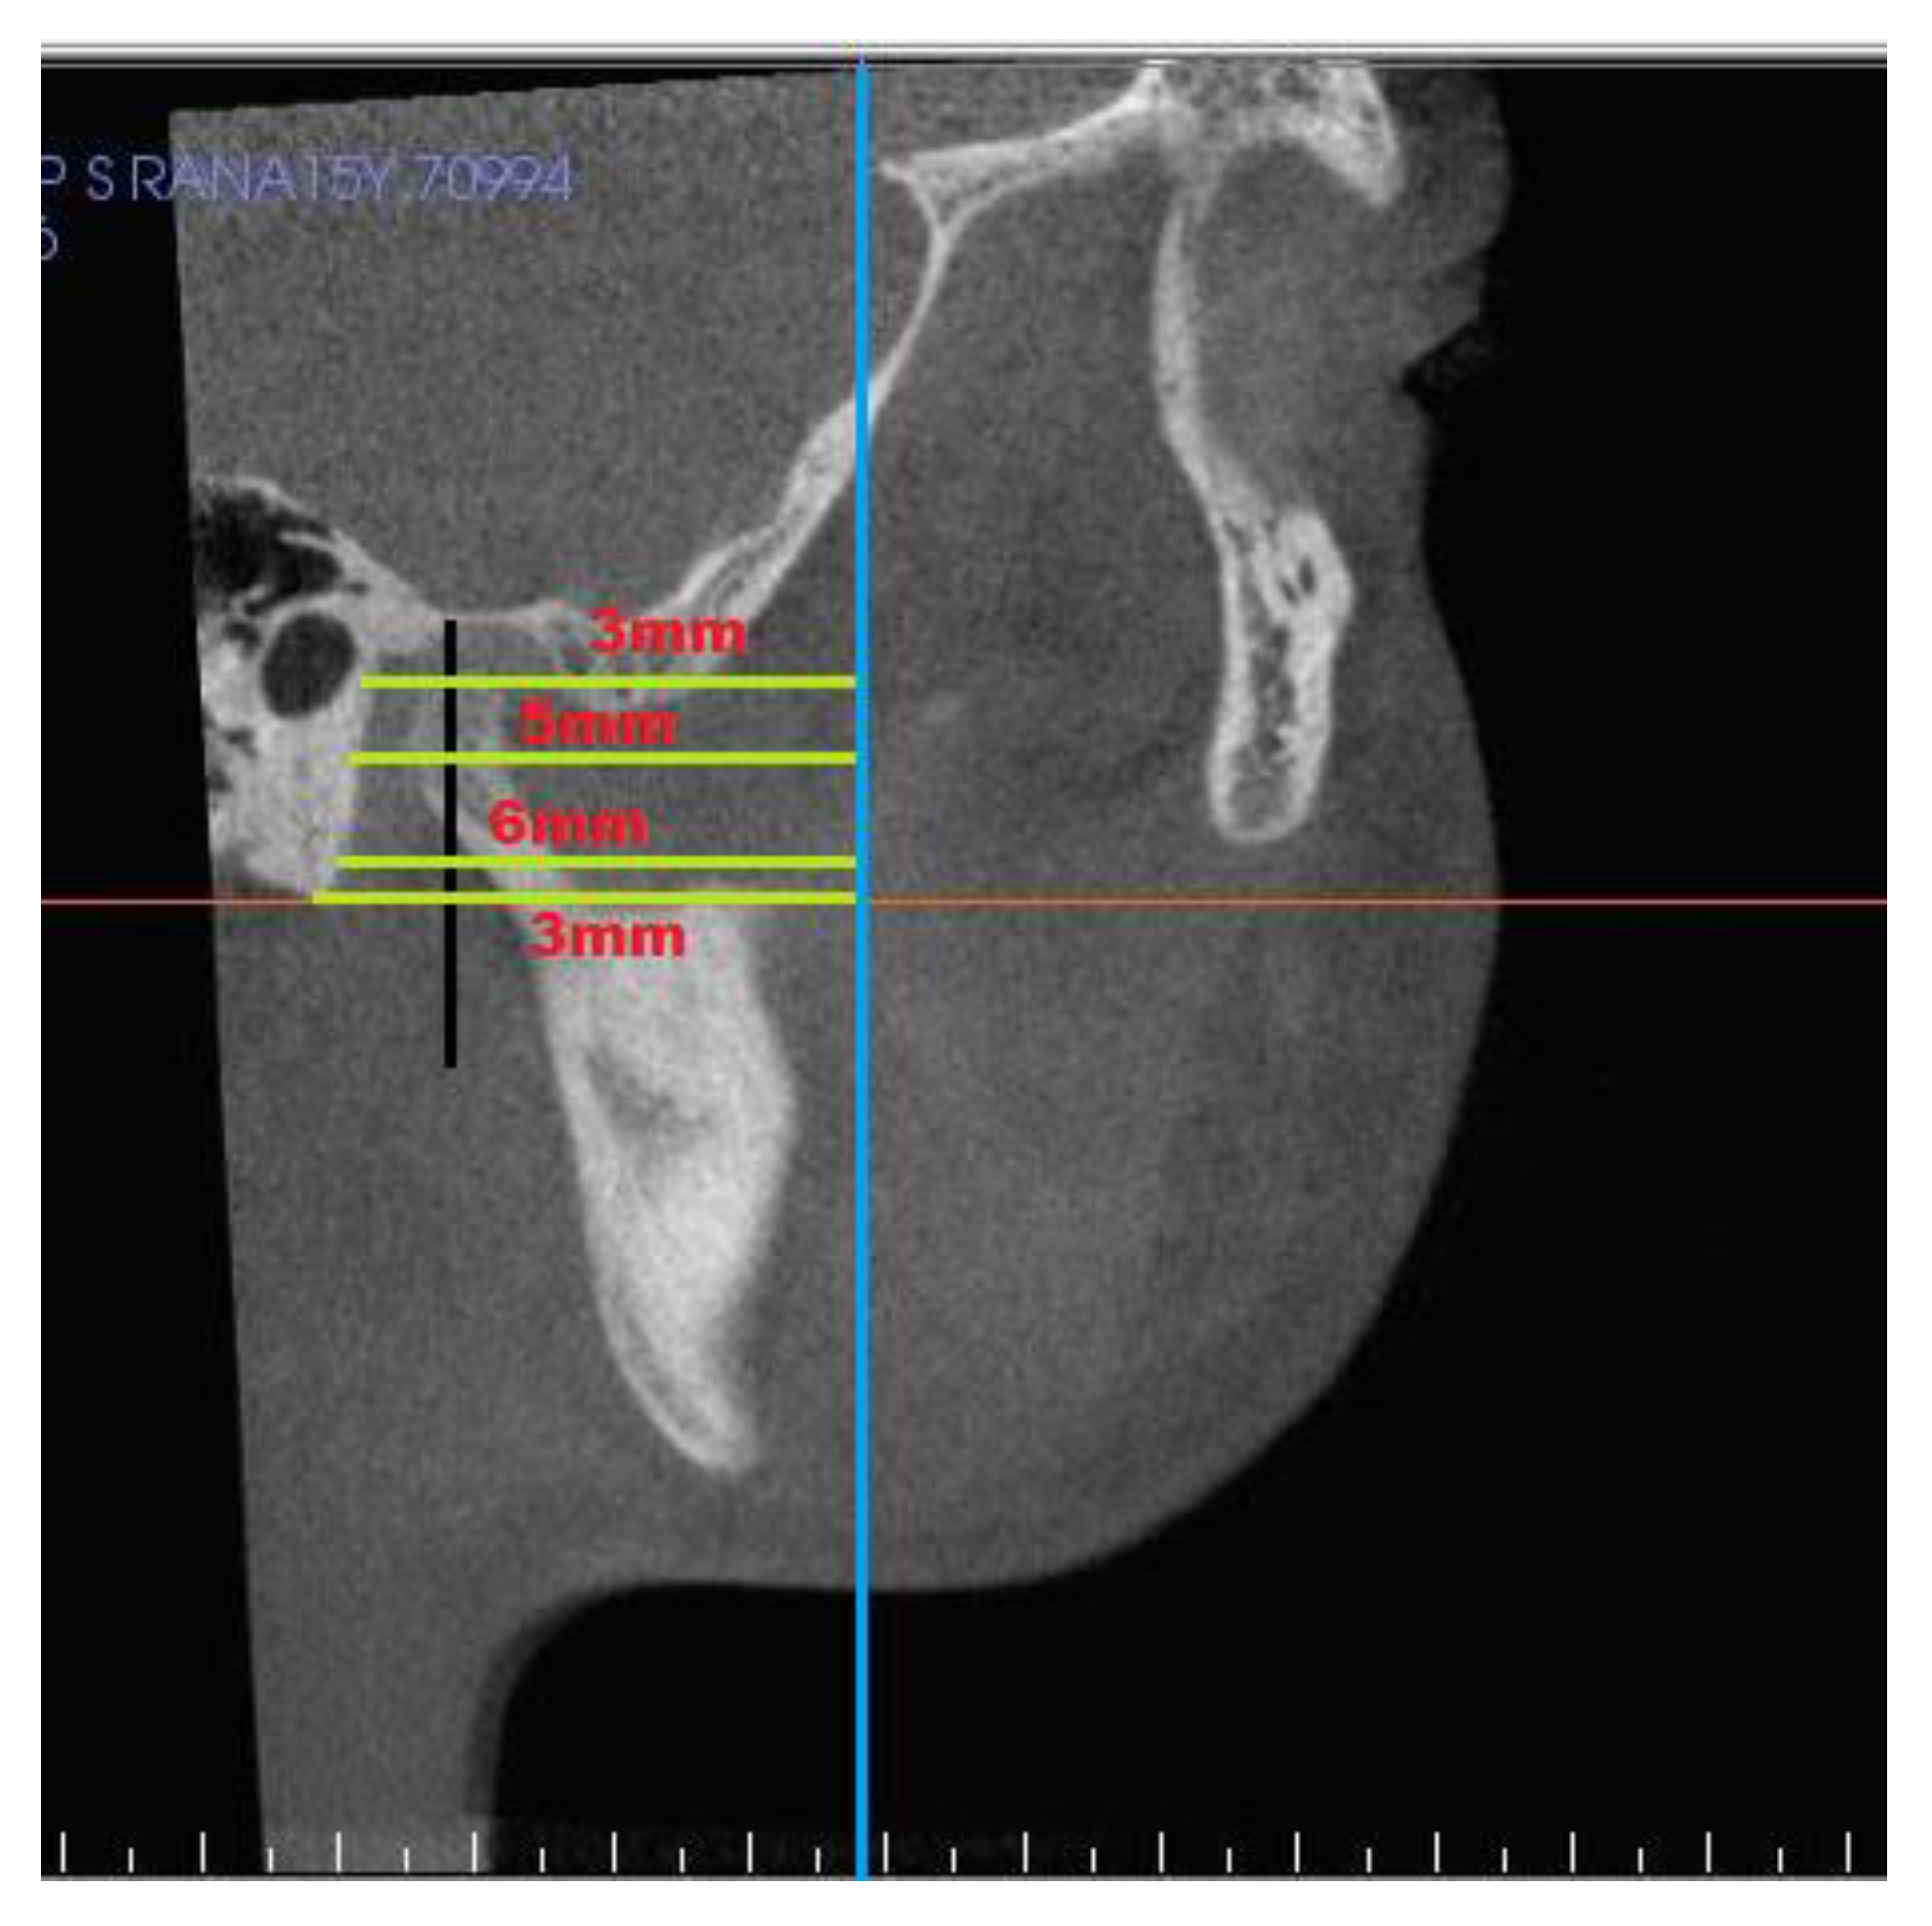

| S. No. | Measurments | Definition |

|---|---|---|

| Condyle | ||

| 1 | Superior joint space | Linear distance from superior point on condyle to highest point on glenoid fossa |

| 2 | Posterior joint space | Linear distance from posterior point on condyle to posterior surface of fossa |

| 3 | Anterior joint space | Linear distance from anterior point on condyle to a point on articular eminence |

| 4 | SCo–T vertical | Linear distance from superior point on condyle to pterygoid vertical |

| 5 | PCo–PT vertical | Linear distance from posterior point on condyle to pterygoid vertical |

| Glenoid fossa | ||

| 6 | ACo–PT vertical | Linear distance from anterior point on condyle to pterygoid vertical |

| 7 | PF 1 to PT vertical | At distance 3 mm from superior point of fossa |

| 8 | PF 2 to PT vertical | At distance 5 mm from PF1 |

| 9 | PF 3 to PT vertical | At distance 6 mm from PF2 |

| 10 | PF 4 to PT vertical | At distance 3 mm from PF3 |

| 11 | Condylar height | Distance from SCo to constructed perpendicular line. |

| 12 | Condylar volume | Volumetric analysis of each mandibular condyle after isolating it. |